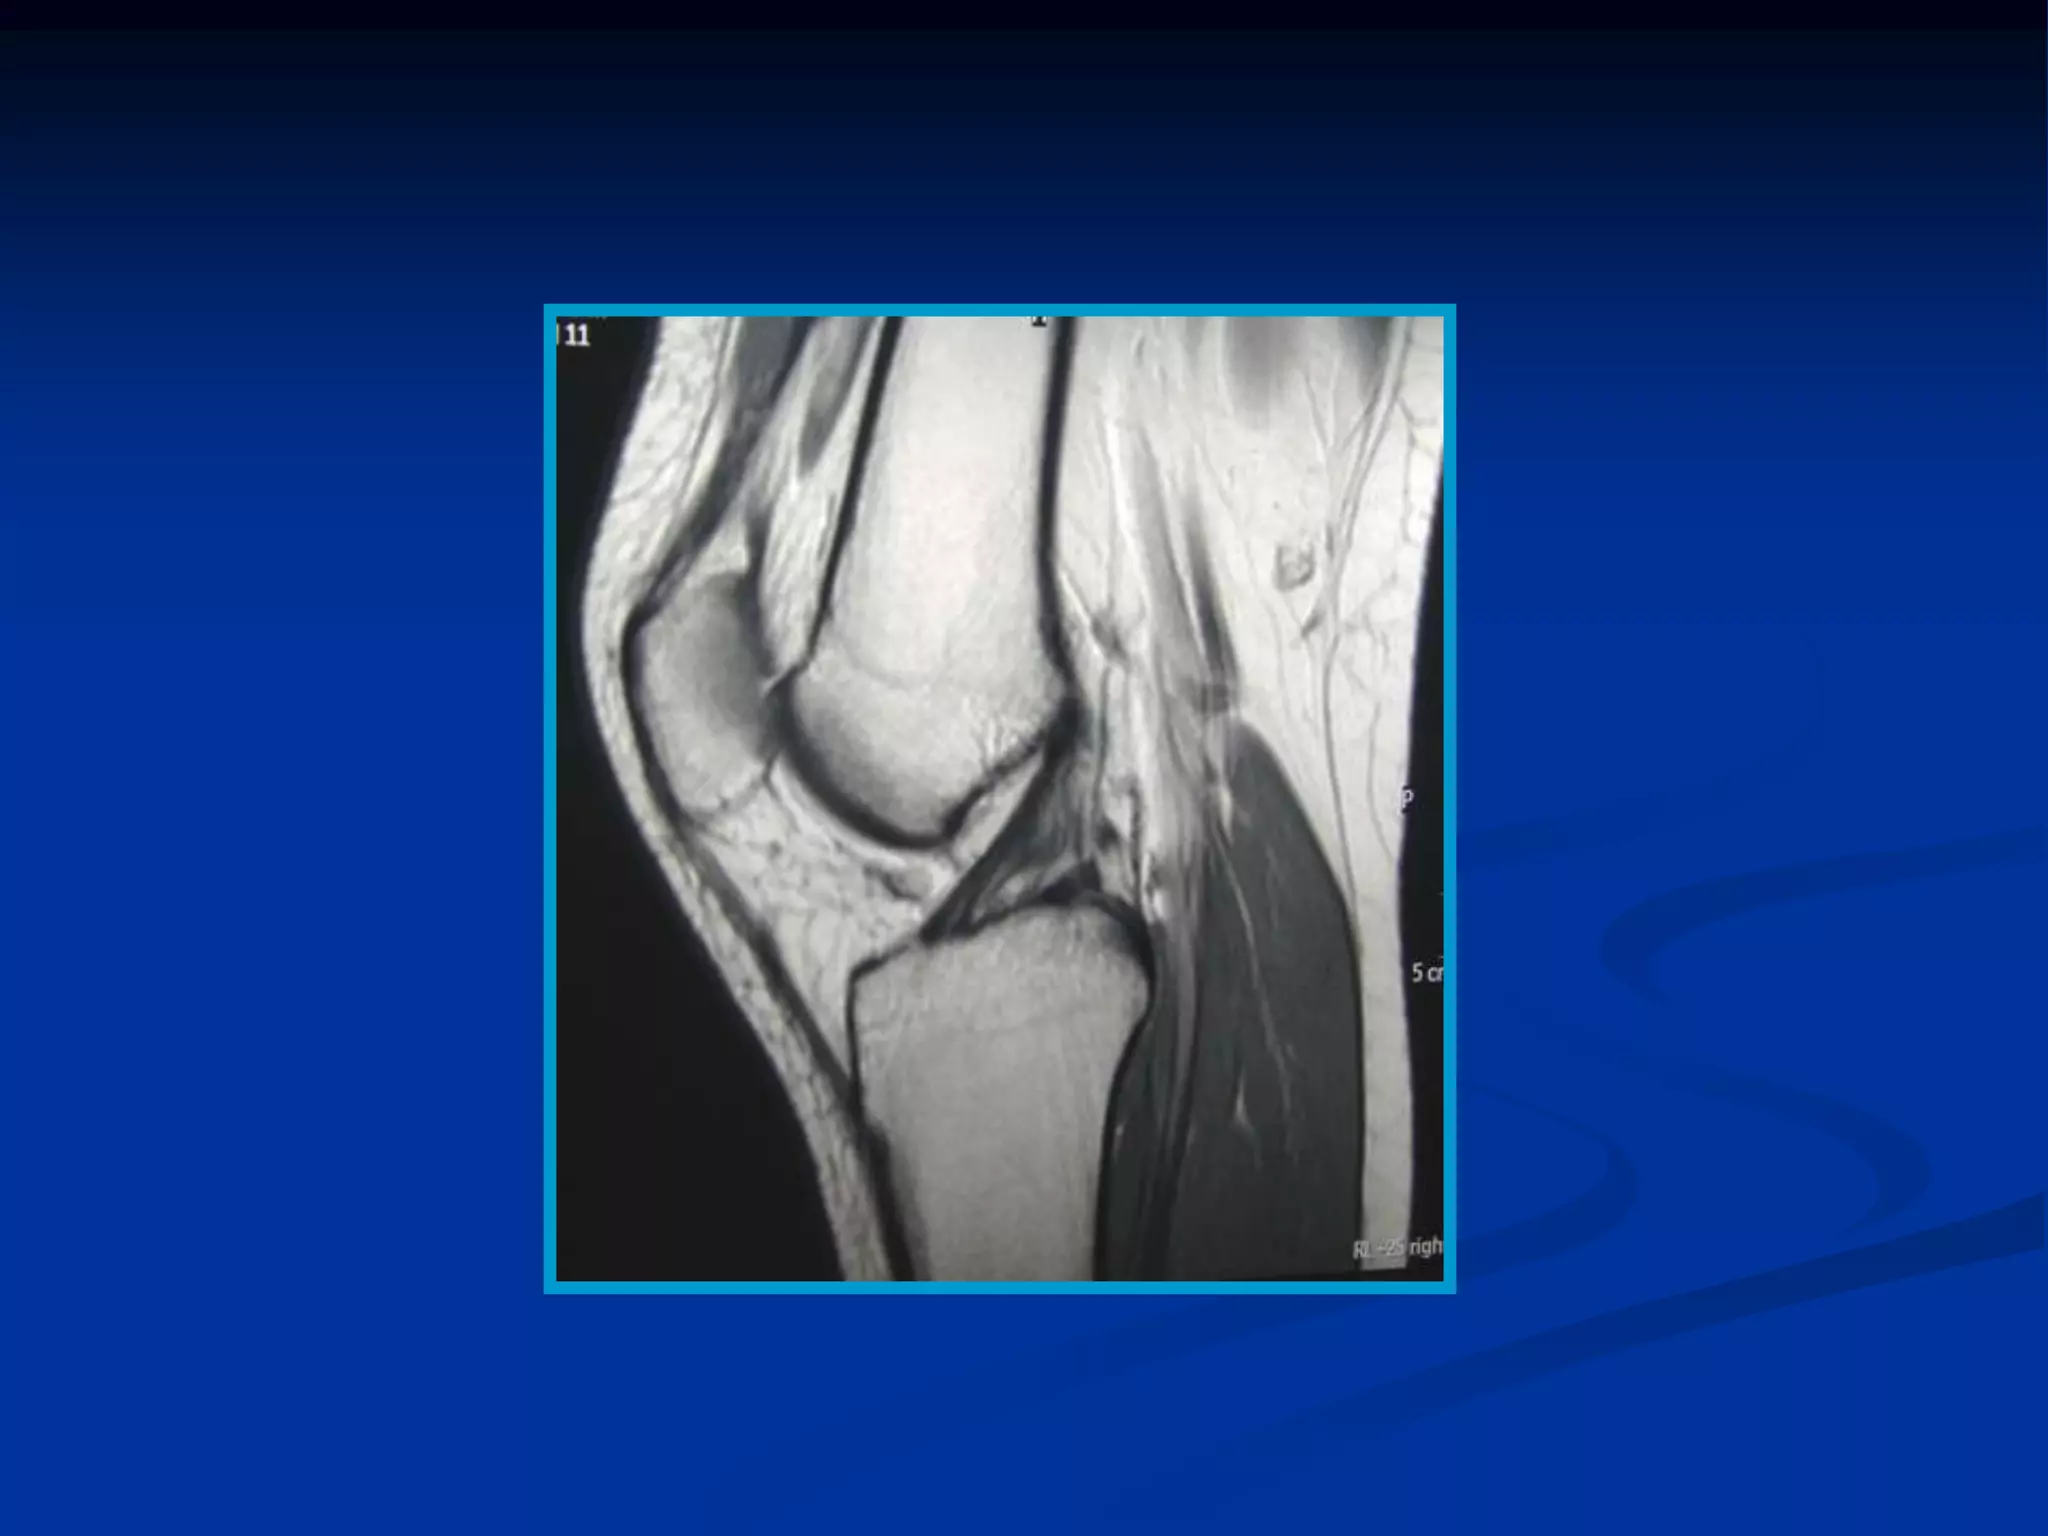

Imágenes potenciadas enT2 de los diferentes tejidos según su grado de relajación T2 en un momento determinado  Los tejidos con liquido y los tejidos patológicos tienen en general un T2 mas largo (mas agua libre) y su señal será mayor (hiperintensa en la imagen).  En la pelvis se muestra acumulo de orina en la vejiga que tiene una relajación T2 largo y en consecuencia una señal intensa en la imagen.

Potenciación en T2  TR (Largo) y TE (Largo) ESTA SECUENCIA SIRVE PARA EVALUAR EDEMA, PATOLOGIA